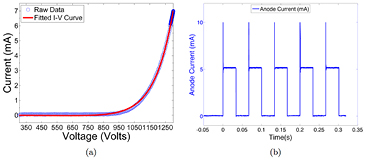

All 75 CNT sources in the array were characterized. Figure 4 shows the field emission properties of the CNT source measured at 80 kVp. As shown in figure 4(a), the emission current versus the applied cathode-gate voltage curve follows the Fowler-Nordheim equation for electron field emission (Gomer 1961). Once the cathode-gate voltage exceeds the CNT field emission threshold voltage, the emission current increases exponentially as the gate voltage increases. The measured transmission rates were consistent among all sources, with an average value of 70%. Figure 4(b) shows the anode current waveform for 5 different sources, measured using an oscilloscope, during source characterization. Each source outputs 5 mA of anode current during a 33 ms pulse width. As demonstrated in figure 4(b), the targeted specification of 5 mA anode current can be achieved with a programmable pulse width and good source-to-source consistency for all sources. The source stability database shows long-term stability for all the CNT x-ray sources used. The source stability for a typical cathode is plotted in figure 5. The cathode-gate voltage showed little change at 5 mA tube current for over 400 scans in four months. This stability is consistently observed from source to source, suggesting that the tube can be stably operated over a long time under this condition.

Figure 4. An example of CNT cathode performance in the x-ray tube. (a) The I-V curve of a CNT cathode shows the voltage needed to extract 7.5 mA of current. (b) The anode current waveforms for 5 mA current and 33 ms pulse width from 5 different CNT sources. The overshot signal at the beginning of each pulse was the step response of the switching electronics, which was not a real anode current overshoot.